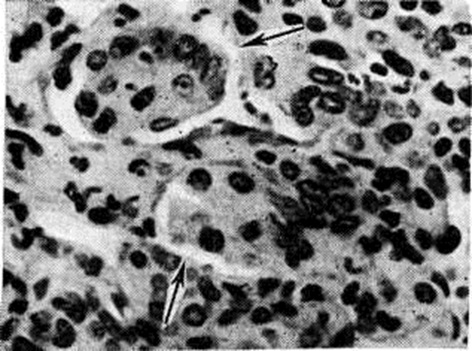

Рис. 1.

Микроскопическая картина эпителиальных клеток бронхов (грипп): стрелками указаны оксифильные включения в цитоплазме (×600).

Характерен серозный, катарально-гнойный, геморрагический и некротический ринит (смотри полный свод знаний), ларингит (смотри полный свод знаний) и трахеобронхит (смотри полный свод знаний Трахеит). В мазках-отпечатках со средней носовой раковины обнаруживается большое количество дистрофизированных клеток цилиндрического эпителия, в цитоплазме которых нередко обнаруживаются оксифильные включения. Наиболее резко поражаются подсвязочная область гортани, трахеи и крупные бронхи (рисунок 1), а также слизистая оболочка языка. Слизистая оболочка — огненно-красная, нередки точечные кровоизлияния и островки желтоватого цвета (очаги некрозов). В более тяжёлых случаях слизистая оболочка трахеи и крупных бронхов на всем протяжении серовато-жёлтого цвета, с небольшими участками кровоизлияний (цветной рисунок 2 и 3). Гистологически эпителий трахеи и бронхов принимает вид аркадообразных структур, возникающих за счёт отёка (смотри полный свод знаний), вакуолизации (смотри полный свод знаний) и отслойки поверхностных слоёв клеток, содержащих вирусный антиген. Часто наблюдается образование фуксинофильных цитоплазматических включений (рисунок 2) и развитие регенераторных (псевдометапластических) процессов. Клетки бронхиального эпителия под действием вируса Грипп теряют ворсинки, количество гранул в них резко уменьшается. Цитоплазматические включения представляют собой аутофагосомы, образующиеся в зоне парциального некроза цитоплазмы вследствие репродукции вируса Грипп (рисунок 3). Резкое полнокровие, отёк и круглоклеточная инфильтрация подэпителиальных слоёв сочетается с утолщением базальной мембраны и усилением секреции образующих слизь желёз. В других местах отмечается гибель эпителия, выраженное полнокровие и лейкоцитарная инфильтрация субэпителиального слоя бронхов и гнойный экссудат с колониями микробов в просвете дыхательных путей. Такого рода очаги гнойно-некротического трахеобронхита служат источником бактериальных поражений лёгочной ткани.